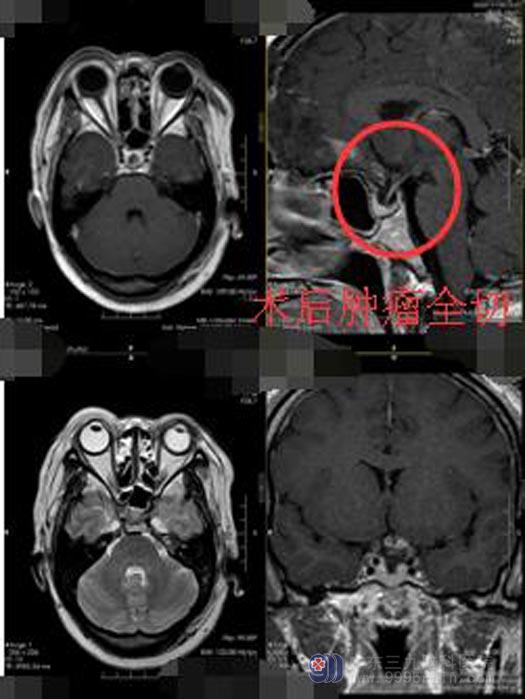

手术切除是治疗鞍结节脑膜瘤最有效的治疗方法,直径小于3cm小型肿瘤较易全切除,可获得治愈的良好效果。左女士及家属同意手术方案。手术中,分离前纵裂蛛网膜及部分导静脉,在蝶骨区可见灰白色肿瘤组织,肿瘤起源于鞍膈,质一般,血供比较丰富,手术主刀鲁明副院长在显微镜下将肿瘤分块切除,双侧视神经与颅内动脉保护良好,垂体体柄位于后部,肿瘤全切,创面止血,术中出血量少,术程顺利。

经过一周左右时间的恢复,左女士感觉自己的两只眼睛视力已经正常,她和病室的病友说笑道:我就说嘛,还这么年轻,没道理眼睛不行了啊。